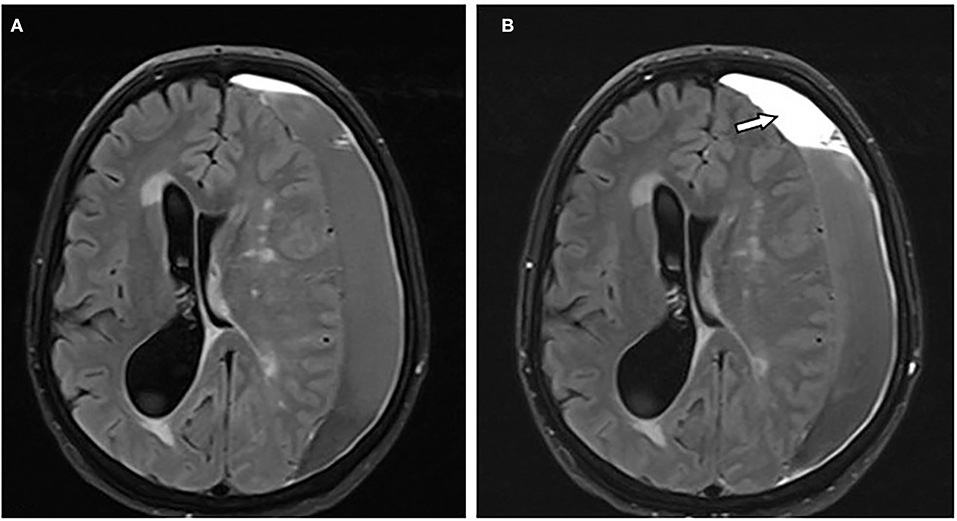

Pada kasus yang ringan, darah yang terkumpul bisa hilang sendiri tanpa perlu intervensi medis. Namun, jika volume darah meningkat, tekanan pada otak bisa semakin besar dan berpotensi merusak fungsi otak. Kondisi ini bisa berbahaya, terutama jika tidak segera didiagnosis dan ditangani. Diagnosis biasanya dilakukan melalui pencitraan medis seperti CT scan atau MRI, yang membantu dokter melihat lokasi dan ukuran hematoma.

Diagnosis subdural hematoma biasanya dilakukan melalui pencitraan medis seperti CT scan atau MRI. Kedua metode ini memungkinkan dokter melihat struktur otak dan mendeteksi adanya perdarahan. CT scan lebih umum digunakan dalam situasi darurat karena prosesnya lebih cepat, sedangkan MRI memberikan detail yang lebih akurat.